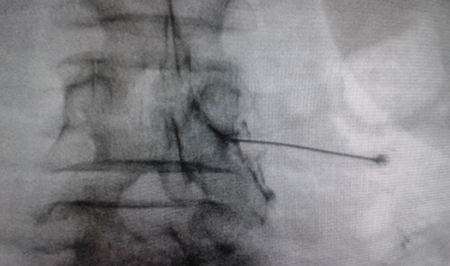

Access by transforaminal route is the most widely used (4). The patient is placed in prone position with an abdominal pillow to reverse physiological lordosis. The most commonly used RF needles or cannulas are 20 or 22 G diameter and 98 mm long with 0.5 or 1 cm active tip. Following asepsis with alcoholic chlorhexidine and placement of sterile fields, radiological approaches in anteroposterior, oblique and lateral incidence are performed. In anteroposterior incidence and moving the arc in cranio-caudal direction, the double arc of the lower vertebral edge is deleted. In oblique incidence between 20 and 30 degrees ipsilateral to the DRG to be treated, the classic image described as “Scotty Dog” will be displayed, which is the result of bringing the articular facets and the spinous process closer to the contralateral side. The entry point will then be immediately below the pedicle. After local anesthesia with 1 % lidocaine, the needle will be inserted following a tunnel vision and will not advance beyond half of the pedicle in this projection to prevent neural injury. In lateral projection, it will be inserted into the roof of the neuroforamen (Figures 1 and 2) but the final location will be determined by sensory-motor nerve stimulation. Sensory stimulation is to cause paresthesia or pain in the affected territory with stimulation between 0.3-0.6 v. During motor stimulation fasciculations can be caused in the affected territory with a voltage of twice that necessary to cause paresthesia. If an intraganglionar denervation, promulgated by some authors, is desired, both sensory and motor stimulation will be positive at less than 0.3 v. As this is a more painful procedure, it is advised to administer local anesthetics after the painful stimulus and before treatment. The impedance should be kept below 450 ohms, which is achieved by infusing saline before proceeding with RF (4). The use of contrast is good practice, as it rules out the intravascular and intrathecal position of the radiofrequency cannula.

Fig. 2. Anteroposterior radiological view of a radiofrequency cannula placed in neuroforamen L4-L5, in the so-called safety triangle, after contrast injection. A thickening of the radiculogram is observed at the roof of the neuroforamen, which may correspond to the dorsal root ganglion of L4